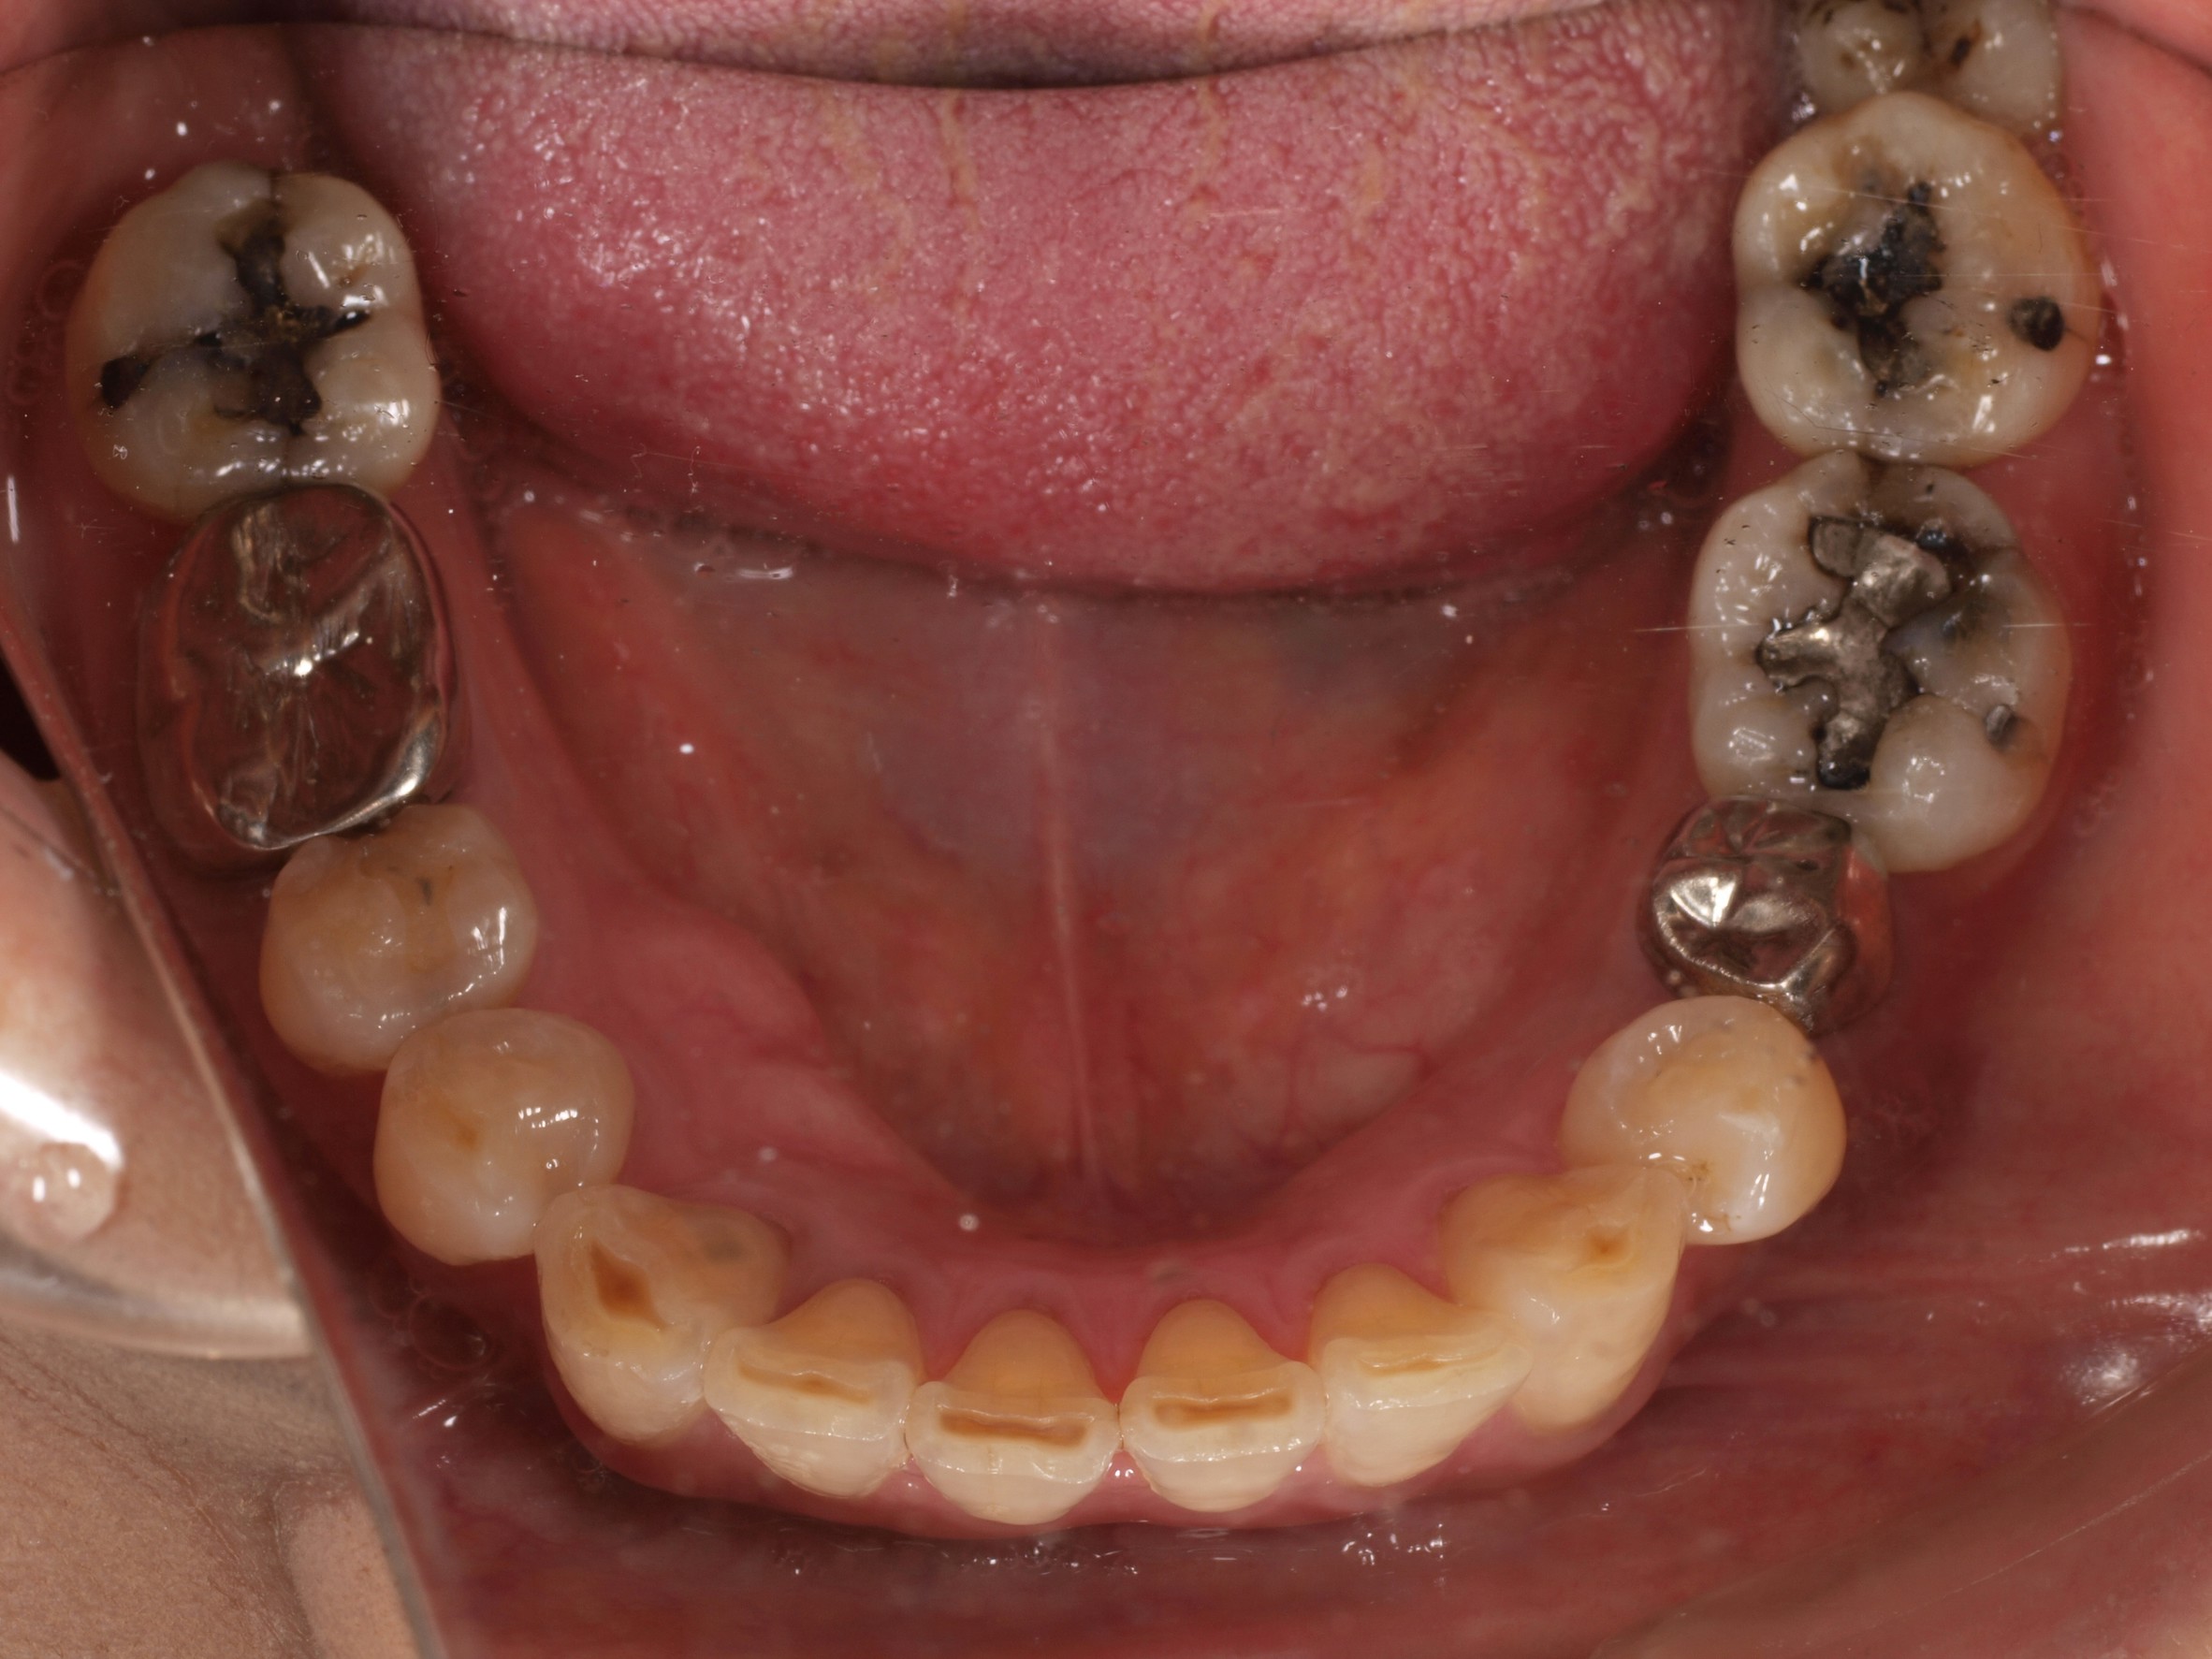

歯周病や虫歯などが原因で、歯がボロボロの状態、歯を失った状態で放置しておくと、歯髄炎や根尖性歯周炎や歯槽膿瘍を引き起こすだけでなく、歯槽骨の吸収も起きるため、最終的には歯を完全に失うことにつながります。また、蜂窩織炎や顎骨骨髄炎などの重大な症状につながることも考えられます。

歯をボロボロの状態にしておくことは、全身への影響も大きく、お口の細菌が、歯茎の血管から全身へ広がり感染症リスクが上昇し、狭心症や心筋梗塞、脳梗塞など発症リスクを高めます。また、歯周病を放置することは糖尿病のリスクを高めるなどの影響もあります。

歯をボロボロの状態にしておくと、さまざまな全身疾患につながるリスクがあるだけでなく、歯を支える骨も徐々に破壊されてしまい、インプラントやオールオン4を入れるための顎骨が残らないケースも少なくありません。

- ・天然の歯がボロボロな状態でありながら、全顎的な歯科治療を必要とされている方

症例紹介

- 主訴

- 入れ歯が気持ち悪く、しっかりと食べれない。本当につらい。美味しく食べて、豊かな人生を過ごしたい。

- 処置内容

- 上顎6本(オールオン6)

- 治療費用

- 上顎350万円(税込)

- 治療期間

- 上顎1年(仮歯まで8か月)/約10回

- リスク

- 上部構造物、仮歯の破折、術後の腫れ(3日)、人工歯根脱落のリスクがあります